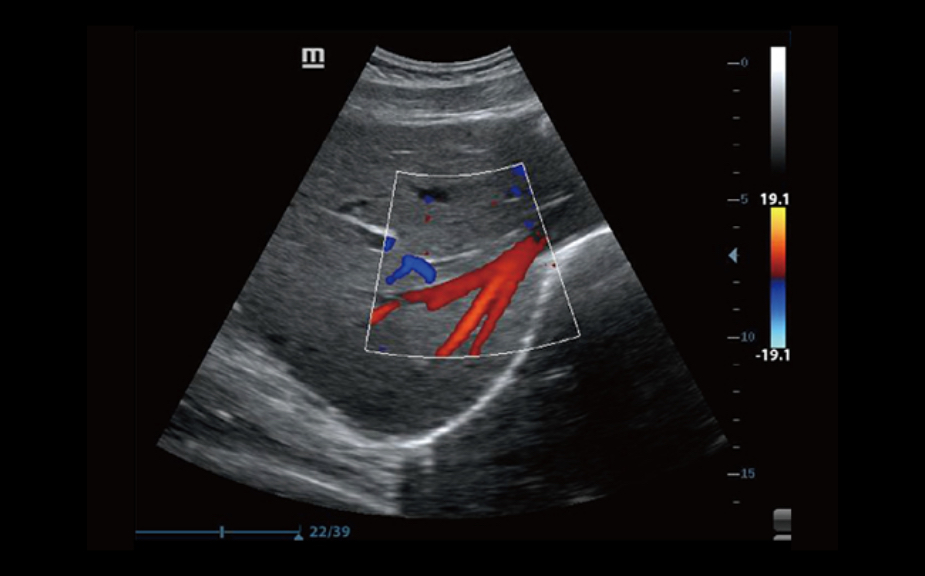

B-Steer?

Narz?dzie pomaga w wykonaniu bardziej precyzyjnej biopsji: umo?liwia ustawianie linii skanowania aby lepiej uwidoczni? ig??, nerwy i drobne naczynia krwiono?ne